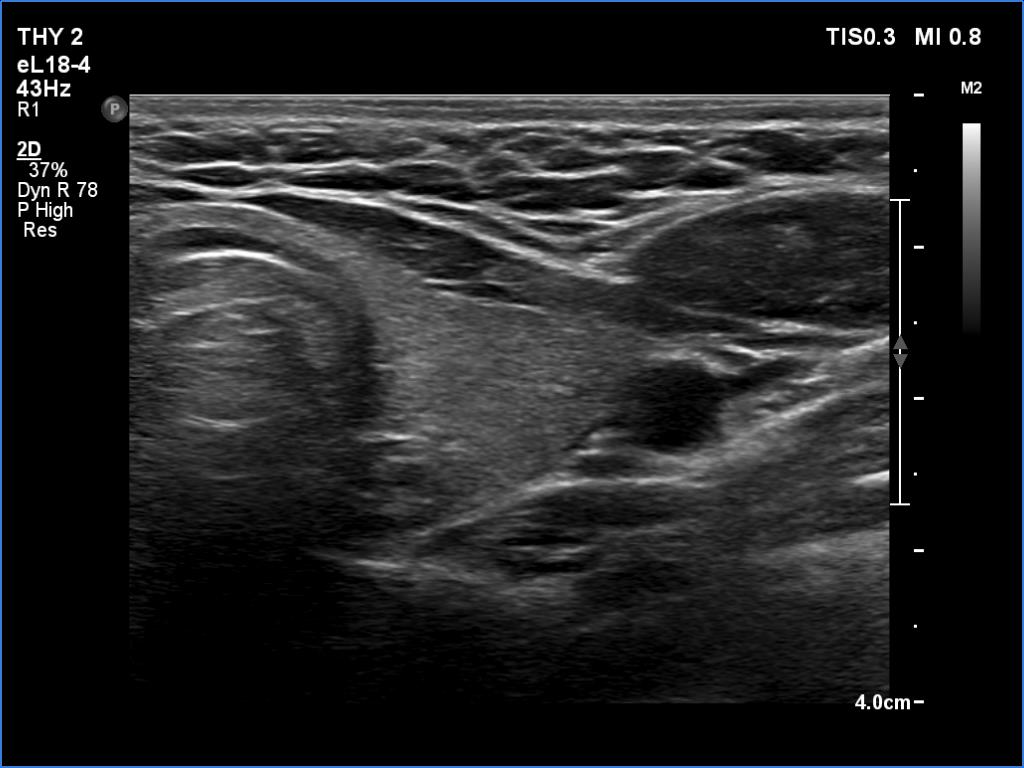

Introduction - case 487 (ultrasonographic picture 11)

Left lobe, transverse scan. This lobe is intact.